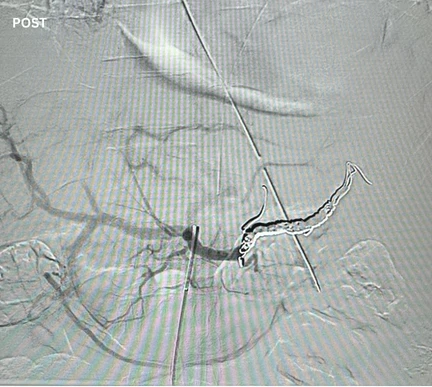

Zoomed in view of Ruby XL Detail

Coils Used: 8mm x 70cm POD XL, 30cm Packing Coil XL, 6mm x 20cm POD XL

Catheter: C2 swapped for a .035″ 90 cm Navicross